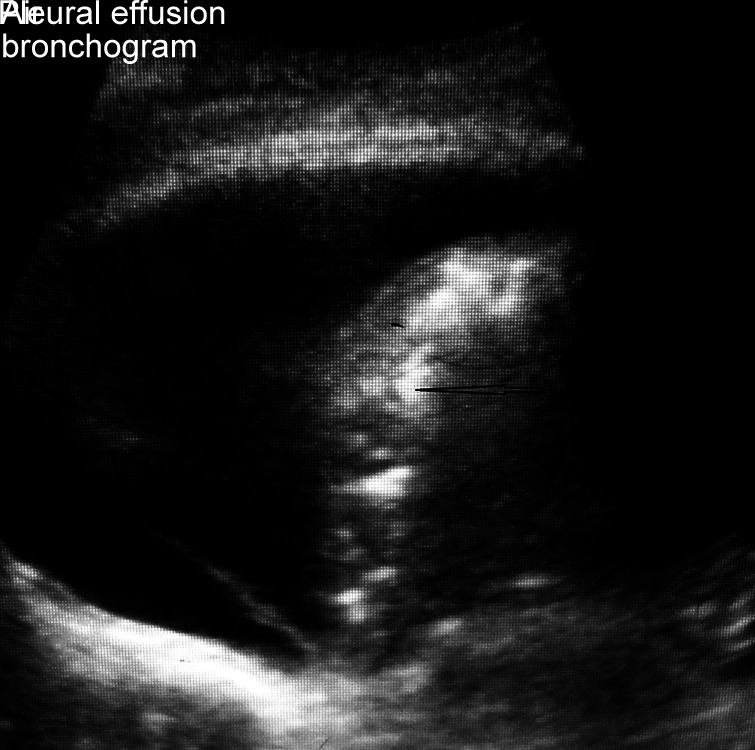

Fig. 3.

Lung ultrasound highlighting air bronchogram within lobar consolidation along with pleural effusion

Lung USG was done to examine areas of abnormality by dividing each hemithorax into three parts with the help of anterior and posterior axillary lines. A horizontal line further divided these parts into upper and lower quadrants, thus making six quadrants in each hemithorax. Lung USG findings were reported as A-lines (normal lung), B-lines (coalescent and non-coalescent), pleural effusions, and consolidation (lobar, subpleural, and areas of dynamic air bronchograms). The presence of dynamic air bronchogram within areas of consolidation (inhomogeneous or tissue-like echotexture), lobar or subpleural consolidation were considered diagnostic of VAP on sonography (Figs 1 to 3).